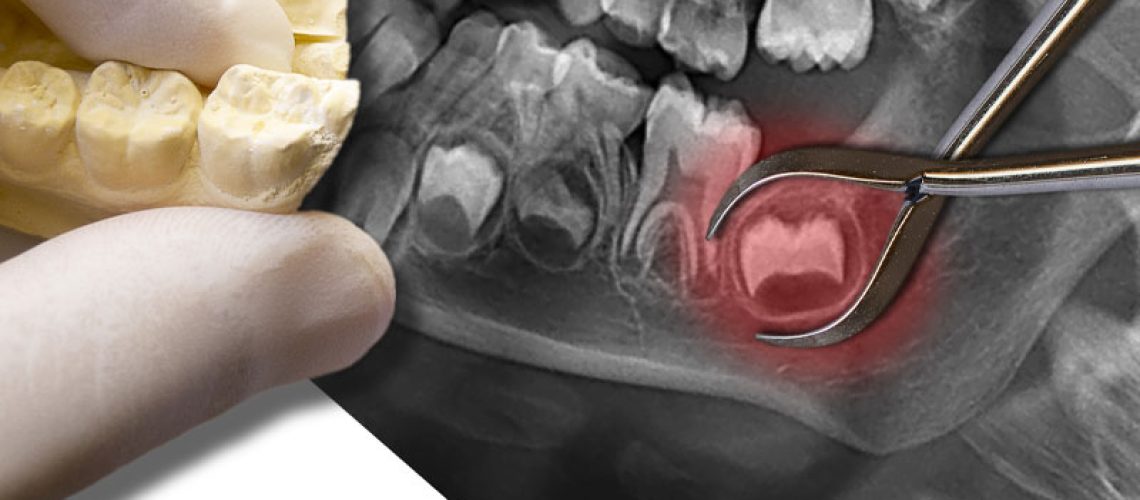

an image of an impacted wisdom tooth.

Say the word “teething” and most people think of a baby. However, adults can have similar painful and uncomfortable symptoms when wisdom teeth are trying to erupt. Also called third molars, wisdom teeth usually come in between the ages of 17 and 25. Impacted wisdom teeth—those that are trapped below the gum line—present the most trouble and problematic symptoms. Read on to learn more about the signs indicating that you may need wisdom teeth removal in Dallas and how the procedure is carefully addressed at Texas Center For Oral Surgery.